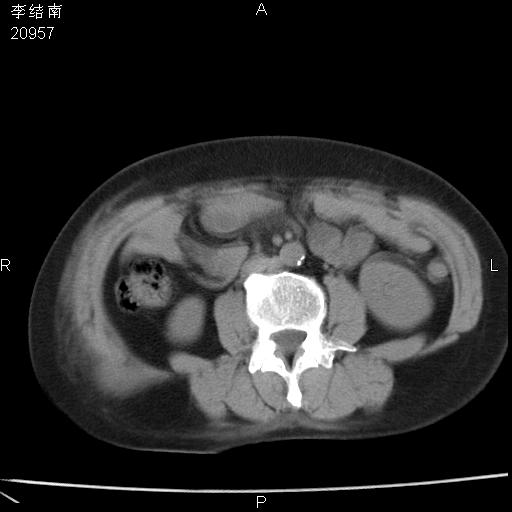

患者女,45岁,以右侧腰部包块来就诊,局部有压痛,皮肤颜色正常。因为是熟人扫的范围较大,患者有胆结石,胆源性胰腺炎病史。请大家看看,有手术病理。

可能大家觉得片子的质量不好,当时是做下腹部扫描,所以没有常规喝水,右腹壁的病灶当时是,密度不均有钙化影,局部骨质没见破坏,肝脏应该是受压的表现,所以当时考虑为腹壁的良性占位,各位老师考虑的神经源性肿瘤,我当时还真没想到,胰腺是胰腺炎治疗后改变.膈脚旁的混杂密度包快不好考虑什么,到上级医院做增强(腹部)+肺部平扫后,发现腹壁的病灶呈不均匀性强化局部可见囊性灶,当时考虑为腹壁结核,最具戏剧性的是膈脚旁的混杂密度灶确是胃的一部分,而腹壁的病灶确是脂肪瘤(简直不可思议)但是我亲眼所见在我们县医院开的.

很不好意思 ,患者后来手术切口裂开,临床医生作了病理证实是腹壁结核。

[病理诊断] CT13183腹壁结核!